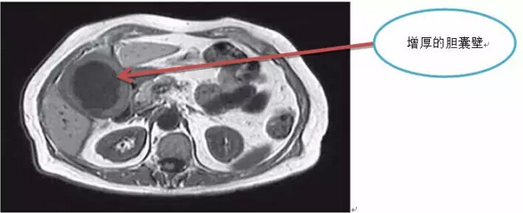

针对B超或CT显示胆囊壁增厚有恶变可能的患者,由于胆囊癌多与胆囊结石炎症并存,故疼痛性质与结石性胆囊炎相似。

影像学检查可见胆囊壁增厚明显,血清CEA值升高。